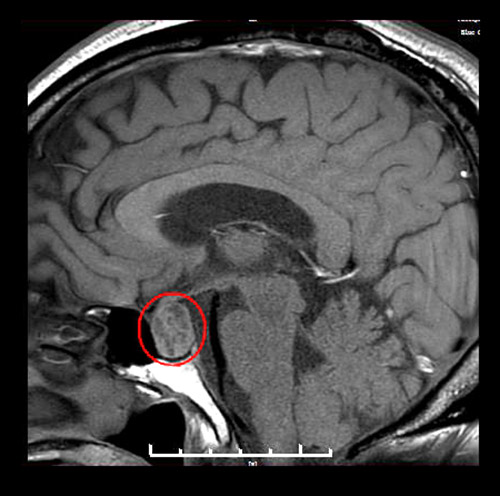

▲術前MR影像:垂體大腺瘤,超蝶鞍生長

神經外科執(zhí)行主任潘仁龍詳細了解了患者的病情,為其完善各項檢查。鞍區(qū)MRI平掃+增強顯示,患者蝶鞍稍擴大,鞍底骨質下陷;鞍內垂體上緣膨隆,腺垂體中央見一枚類橢圓形異常信號,直徑約1.8*1.4厘米。綜合各項檢查結合臨床,王老伯確診為垂體大腺瘤(1~3cm的叫做大腺瘤)。

李士其教授和潘仁龍主任一起,研討了患者病情,由于患者顱內鞍區(qū)的腫瘤屬于大腺瘤,已嚴重影響到患者的垂體功能,并壓迫視神經,感覺神經等功能,所以出現頭暈、視力模糊。